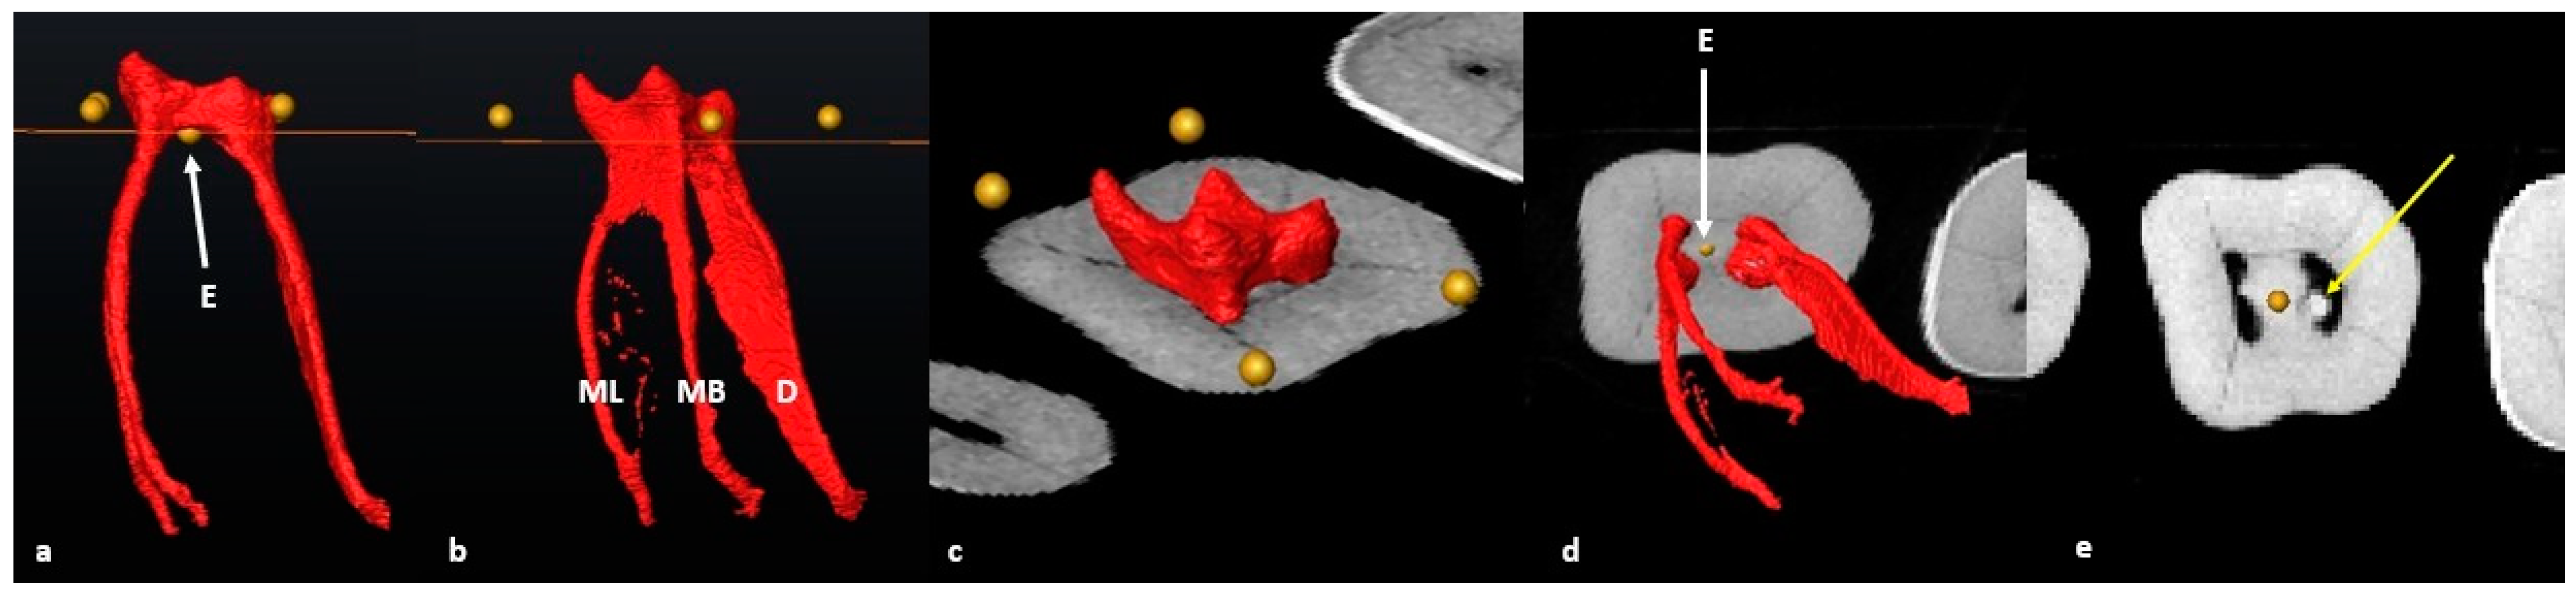

2.6. Segmentation and Landmark Identification

3.1. Mandibular First Molars: Two Rooted